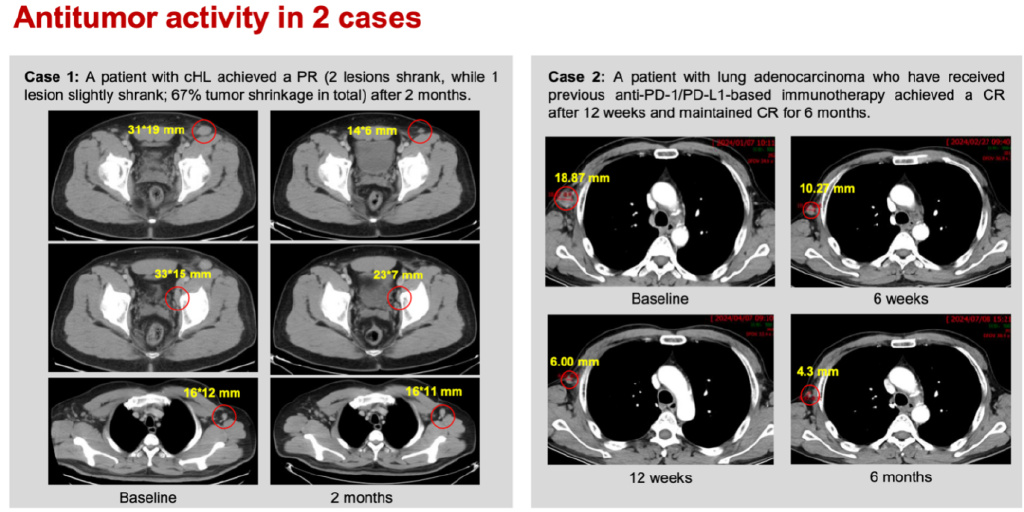

典型病例:

病例1:一例复发的经典型霍奇金淋巴瘤患者在BPI-371153治疗2个月后肿瘤缩小67%,达到部分缓解(PR)。

病例2:一例既往接受过PD-1/PD-L1免疫治疗的肺腺癌患者在BPI-371153治疗12周后达到完全缓解(CR),并维持CR达6个月。(图5)

图5. 病例